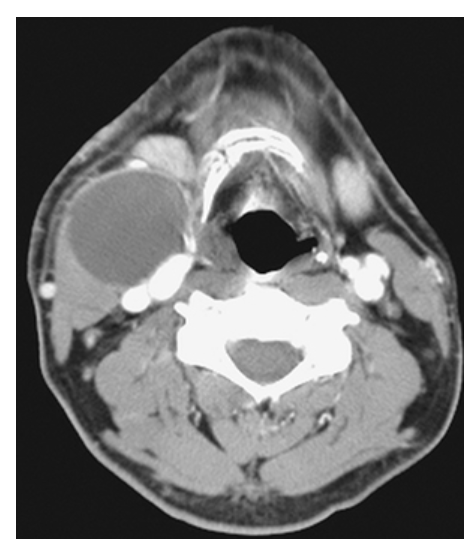

What does the figure show?

Brachial Cleft Cyst. Axial contrast-enhanced computed tomography (CECT) shows a cystic lesion in the right neck of a child located anteromedial to the sternocleidomastoid muscle, posterolateral to the submandibular gland, and lateral to the carotid space. In a child, this is a classic location and appearance for a second type BCC. Other differential considerations would include suppurative lymphadenitis or necrotic lymph node metastases (in an adult).